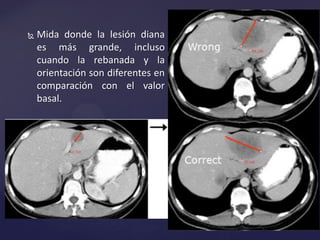

 Mida donde la lesión diana

es más grande, incluso

cuando la rebanada y la

orientación son diferentes en

comparación con el valor

basal.

 Mida dondela lesión diana es más grande, incluso cuando la rebanada y la orientación son diferentes en comparación con el valor basal.